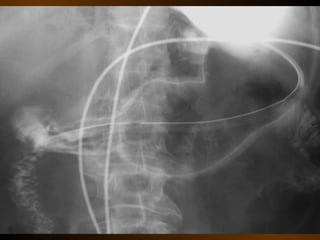

KHÍ TỰ DO

TRONG KHOANG PHÚC MẠC

NGUYÊN NHÂN

thủng tạng rỗng

nguồn gốc xuyên phúc mạc

nguồn gốc trong phúc mạc

10 – 15% thủng tạng rỗng → không thấy hơi tự do ổ bụng

KHÍ TỰ DO TRONGKHOANG PHÚC MẠC NGUYÊN NHÂN thủng tạng rỗng nguồn gốc xuyên phúc mạc nguồn gốc trong phúc mạc 10 – 15% thủng tạng rỗng → không thấy hơi tự do ổ bụng